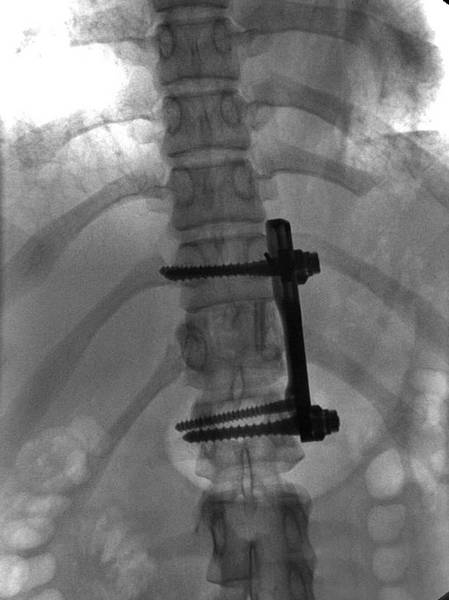

Повреждение позвоночника (с опасностью паралича) проявляется на ладони извилистой линией, проходящей вне пределов большого треугольника в проекционной зоне грудного отдела позвоночника, выпускающей мелкие линии в направлении холма Луны. На рисунке 1.88 приведена рука молодой девушки с переломом грудного отдела позвоночника, который произошел в результате ДТП, а на рисунке 1.88–1 – ее рентгеновский снимок, который был сделан спустя год с момента данного события. При сравнении знака на ладони с металлическим фиксатором в позвоночнике девушки бросается в глаза наглядное сходство вставленной в позвоночник пластины со схематически прорисованным на ее ладони знаком в соответствующей проекционной области. Подобное совпадение помимо визуального сходства указывает еще и на сильные физические страдания и боли в позвоночнике по настоящее время, о которых говорит глубокий и не спешащий сойти с руки знак. Помимо данного знака на ладони присутствует еще и общий признак травмы грудного отдела позвоночника, выраженный в резком смещении серединного участка линии Жизни в сторону холма Венеры.

Рис. 1.88

Рис. 1.88–1